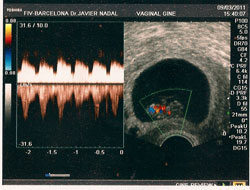

En un proceso de FIV, la mujer debe realizar un tratamiento de estimulación ovárica con medicamentos inductores de la ovulación, cada día más puros y eficaces, para intentar conseguir el máximo número de folículos. Estos tratamientos son siempre personalizados para cada paciente y dependerán de factores como la edad y de los resultados de las analíticas hormonales previas, y supervisados siempre con controles ecográficos y analíticos.

Una vez los folículos alcancen el número y el tamaño idóneo, se administra una nueva medicación para provocar la maduración ovocitaria.